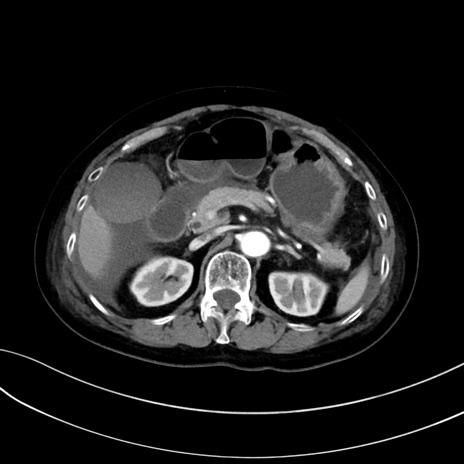

症例13 CT(横断像)1日半後